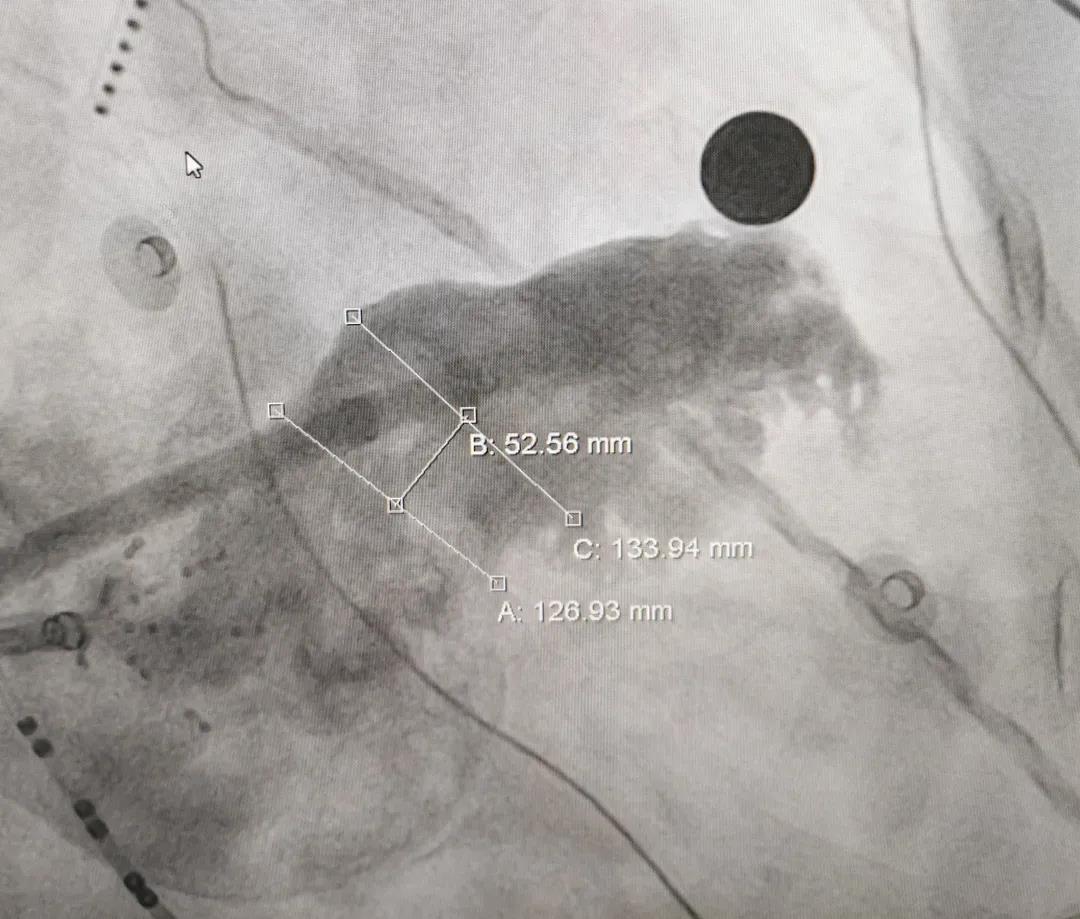

患者男,63岁,间断心悸病史11年。术前TEE显示左心耳无血栓,拟行房颤射频消融联合左心耳封堵术。左心耳测量锚定区约为27mm,封堵区约为25mm,选用LAmbre™2632封堵器进行封堵,达到了理想的封堵效果。LAmbre™独特的锚定机制能确保左心耳封堵器稳定牢固,牵拉测试十分稳定,符合COST原则,随后释放封堵器。